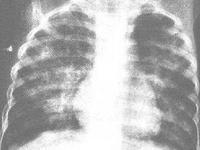

单纯性肺嗜酸粒细胞浸润症是怎么回事?吕弗琉于1932年首先描述本病,故又名吕弗琉综合征。其特点为游走性肺部浸润伴外周血嗜酸粒细胞计数增高,肺部症状轻微,多数仅有轻咳,病程呈自限性,常于3~4周内自行痊愈。本症很可能为肺泡的一过性变态反应,常见病因为寄生虫感染和药物反应。约有1/3患者未能查出病因。本病在某些地区呈季节性流行,故推测环境抗原因素在某些地区亦为可能的病因。[1]